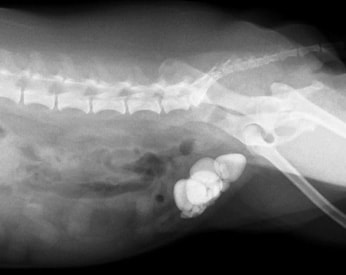

膀胱結石

膀胱結石とは、膀胱内に結石が作られて、慢性的に頻尿、血尿、膀胱炎を起こします。

放っておけば、結石はどんどん大きくなり、膀胱や腎臓に負担がかかり、腎不全や、膀胱腫瘍に移行してしまう事があります。なるべく早めの外科的摘出をおすすめします。

![]() 【レントゲン写真】膀胱内に大きく白い結石が確認されます。 |

|